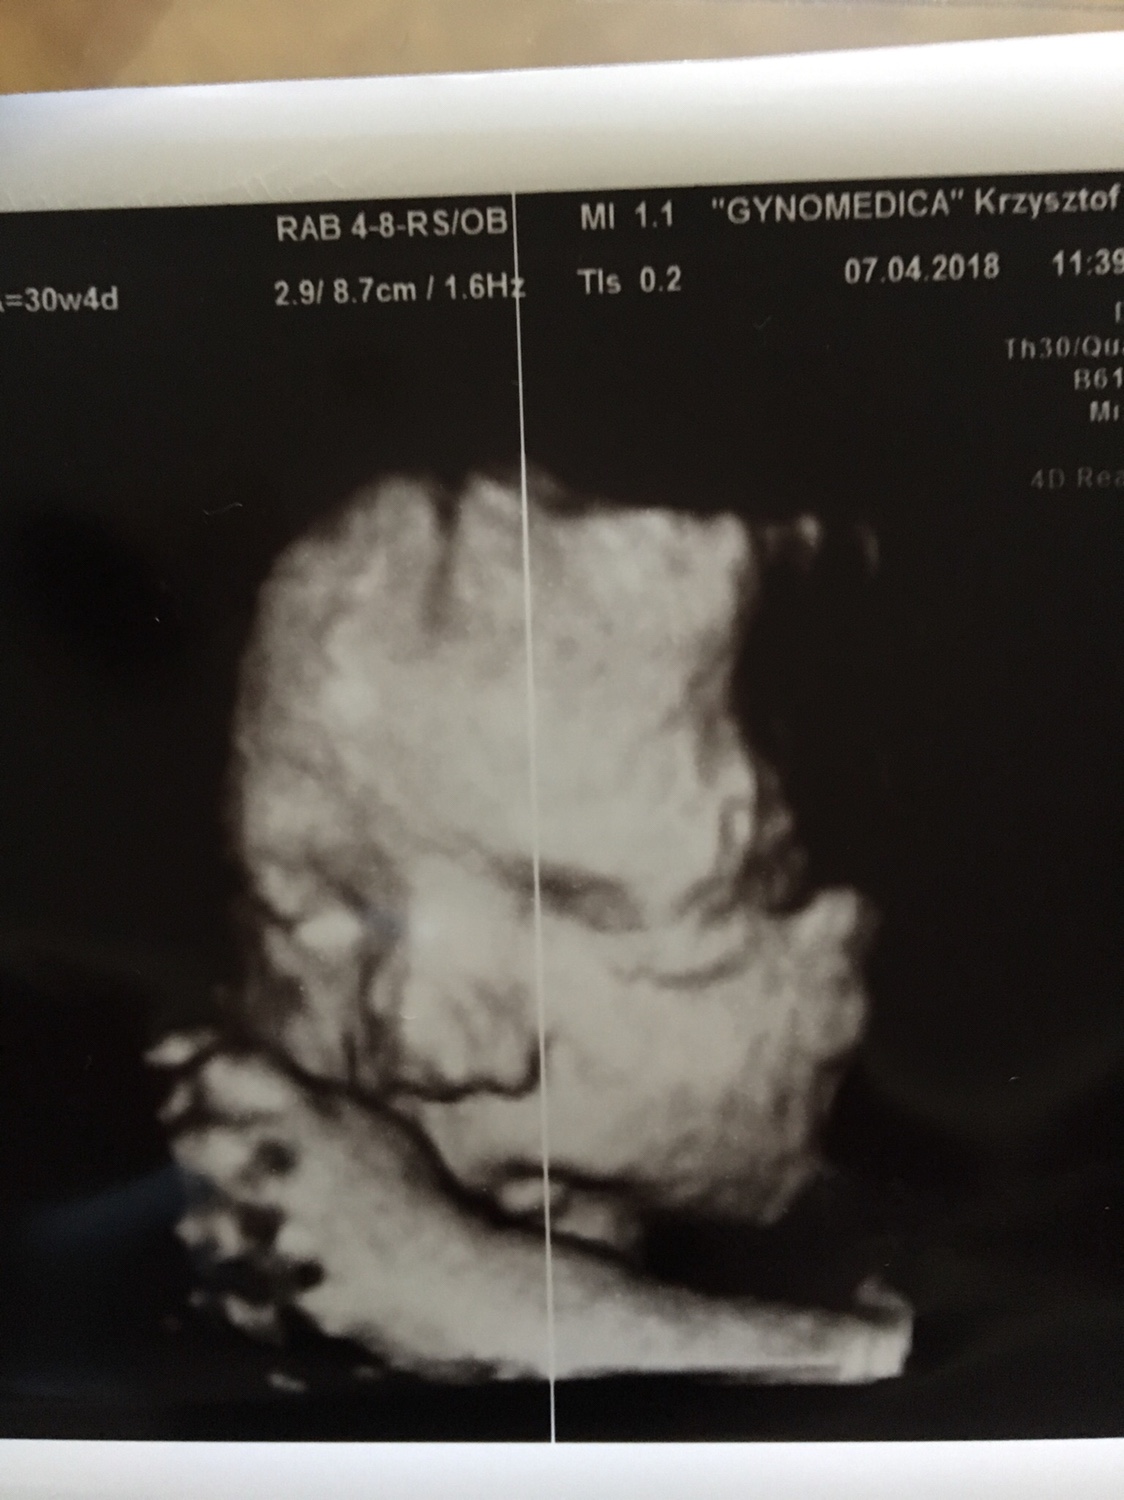

Wczoraj mieliśmy wizytę u lekarza. 32 tyg, mała ma 1286g, drobniutka będzie albo jeszcze nadrobi

mam zdjęcia z usg 3d, później wstawię